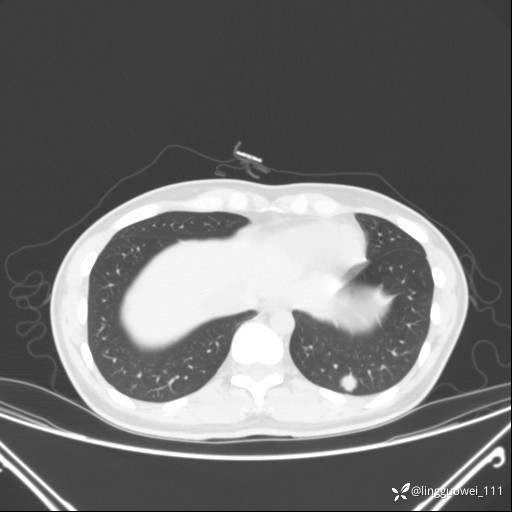

患者性别:女

患者年龄:26岁

主诉:咳嗽来诊,结节性质不明。

肺毛细血管瘤 (2)